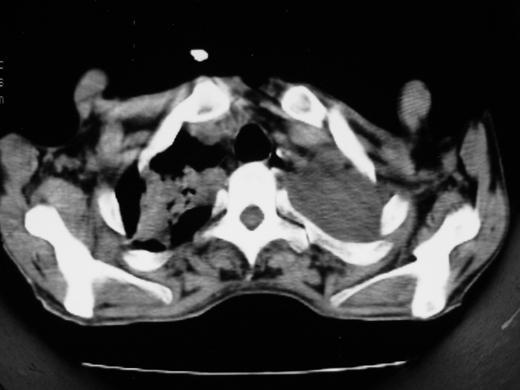

男69岁,年前胸片示肺感染治疗近一月今复查无明显好转,血象正常

双肺内不规则斑点状 片状及结节密实影,部分灶周见索条样影及\"树芽征\",左肺上叶实变,内见充气支气管影及斑状钙化,左侧少量胸腔积液,考虑1)双肺结核2)左侧胸腔积液

右肺多发片絮状结节状及时条索状影,左上肺实变,内可见虫蚀样空洞及支气管气象,左下肺片状及球形病灶,及胸腔积液征象,双肺病灶内多发钙化影,结合病史,考虑双肺继发型肺结核,左胸腔积液

右肺多发片絮状结节状及时条索状影,左上肺实变,内可见虫蚀样空洞及支气管气象,左下肺片状及球形病灶,及胸腔积液征象,双肺病灶内多发钙化影,上纵隔向左侧移位,结合病史,考虑双肺继发型肺结核,左胸腔积液。

右肺多发片絮状、结节状及条索状影,左上肺实变,内可见虫蚀样空洞及支气管气象,左下肺片状及球形病灶,有胸腔积液征象,双肺病灶内多发钙化影,上纵隔向左侧移位,结合病史,考虑双肺继发型肺结核,左胸腔积液。 建议结合ppd检查或纤支镜检查!

右肺可见大片状、云絮状改变。右肺可见散在类圆形影,以外带多见。左肺实变,其内可见明显支气管走行影。纵隔淋巴结有增大,左侧胸腔积液。考虑1、肺结核;2、肺癌肺转移不除外;3、左侧胸腔积液。